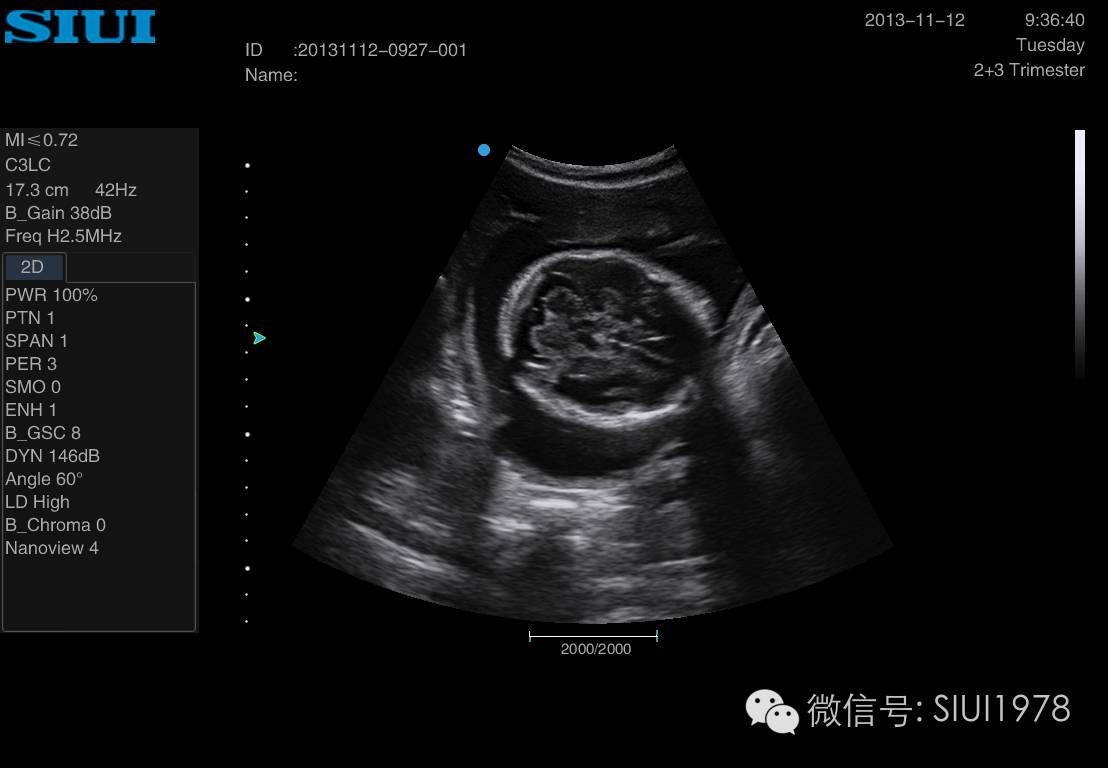

胎儿侧脑室超声切面图,胎儿脑部超声切面图解

胎儿系统超声检查切面及临床意义一

脑中线 侧脑室 侧脑室水平解剖学标志 透明隔,侧脑室前角顶端 脑室

胎儿标准切面 侧脑室

侧脑室切面

看丘脑,透明隔,脑中线,颅骨光环,头皮厚度,顺便晃动探头,看看侧脑室